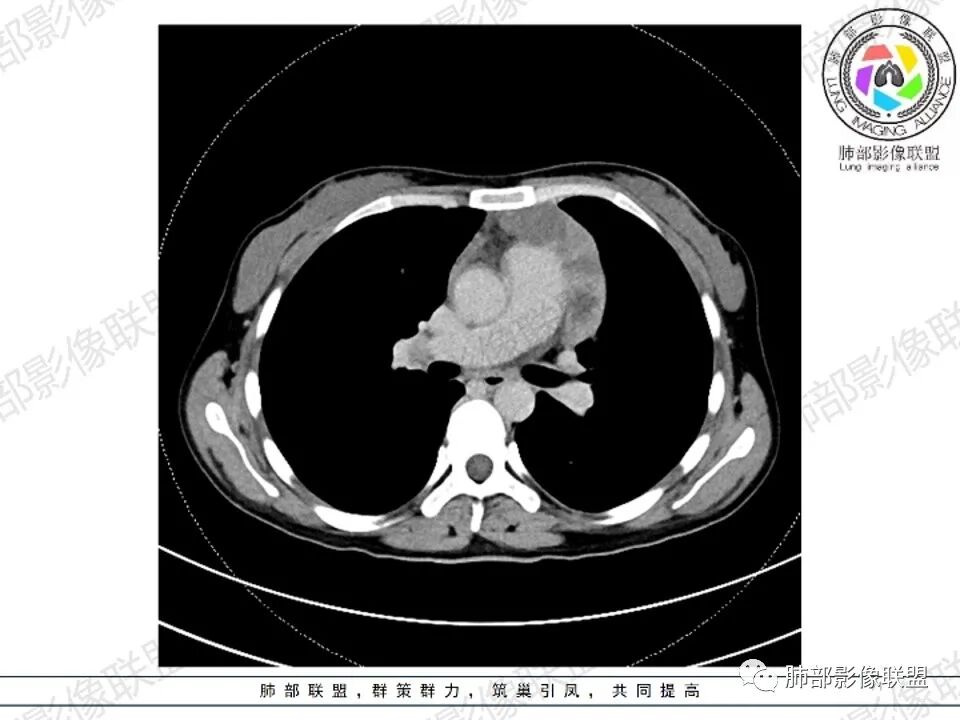

2.影像显示前纵隔不规则块状影,依势贴附心脏大血管旁,密度不均,边界不甚清楚,有结节融合感。

3.病灶轻度不均匀强化,可见血管穿行,散在液性低密度区。

双肺门未见肿大淋巴结。

4.双侧腋窝区见增大淋巴结,边界清楚。